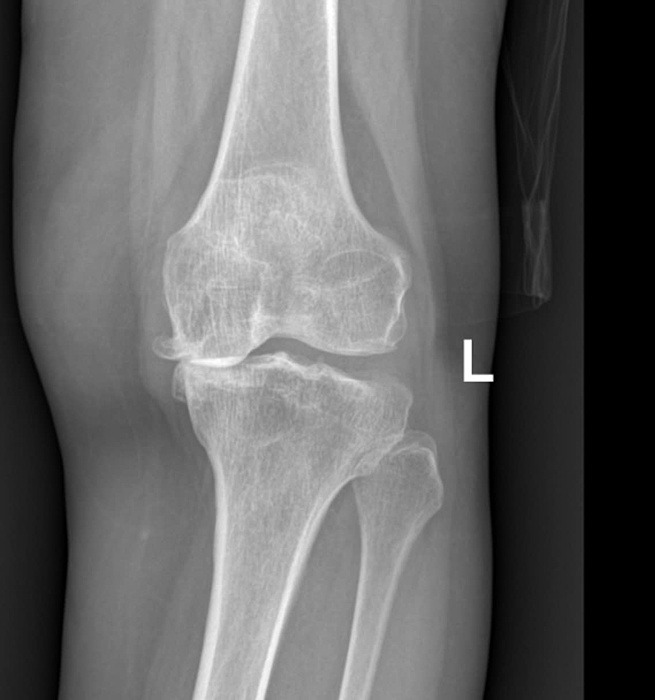

Old  Default Nguyên nhân gây thoái hóa khớp

Thừa cân, chấn thương, tập thể dục quá mức hay ít vận động là những nguyên nhân gây ra hoặc thúc đẩy thoái hóa khớp diễn ra nhanh, nghiêm trọng hơn.

Sụn khớp là lớp đệm bao phủ bề mặt xương, cấu tạo từ tế bào sụn và chất căn bản. Sụn khớp có chức năng bảo vệ, giảm ma sát trong khớp và đóng vai tṛ như "bộ giảm xóc". Sụn và các mô xung quanh khớp bị tổn thương được gọi là thoái hóa khớp.

ThS.BS Phạm Thị Xuân Thư, Đơn vị Nội cơ xương khớp, Pḥng khám Đa khoa Tâm Anh Quận 7, cho biết thoái hóa khớp là một phần của quá tŕnh lăo hóa tự nhiên. Khi tuổi tác ngày càng cao, sụn khớp có xu hướng mỏng dần, dịch khớp có tác dụng nuôi dưỡng sụn và bôi trơn khớp ngày càng giảm cả về số lượng lẫn chất lượng. Khi t́nh trạng này diễn ra trong thời gian dài, sụn khớp dễ bị tổn thương, gây bong nứt sụn, gia tăng ma sát giữa khớp, dẫn đến đau và thoái hóa.

Chấn thương: Đây là nguyên nhân có thể trực tiếp làm tổn thương sụn khớp, dẫn đến thoái hóa. Chấn thương cũng có thể tạo điều kiện thuận lợi cho viêm khớp phát triển, làm tổn thương các cấu trúc mềm như dây chằng và gân. Nếu viêm kéo dài có thể làm hỏng sụn và xương, đẩy nhanh tốc độ thoái hóa khớp.